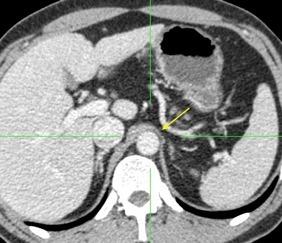

3 rasgos: Conexión entre mediastino y lesión pancreática. Derrame pleural Hallazgos de pancreatitis. Matsusue E et al.Three cases of mediastinal pancreatic pseudocysts. Acta Radiol Open. 2016 .

Aneurisma aórtico intracrural

/Restrepo CS et al. The diaphragmatic crura and retrocrural space: normal imaging appearance, variants, and pathologic conditions. Radiographics 2008